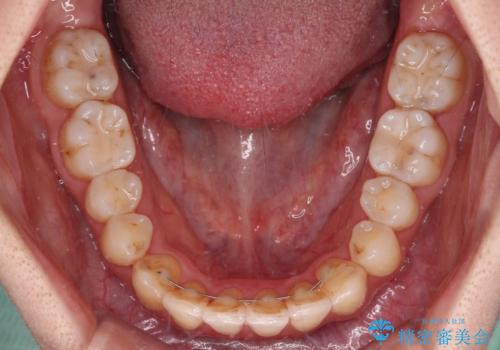

【モニター】前歯の前突感とクロスバイトをインビザラインで改善

舌側転位している側切歯特有の、切縁の位置が不揃いであったり、根元が内側に引っ込んだ状態であったりという、インビザライン独特の仕上がりになることなく、きれいに整った歯列とすることができました。